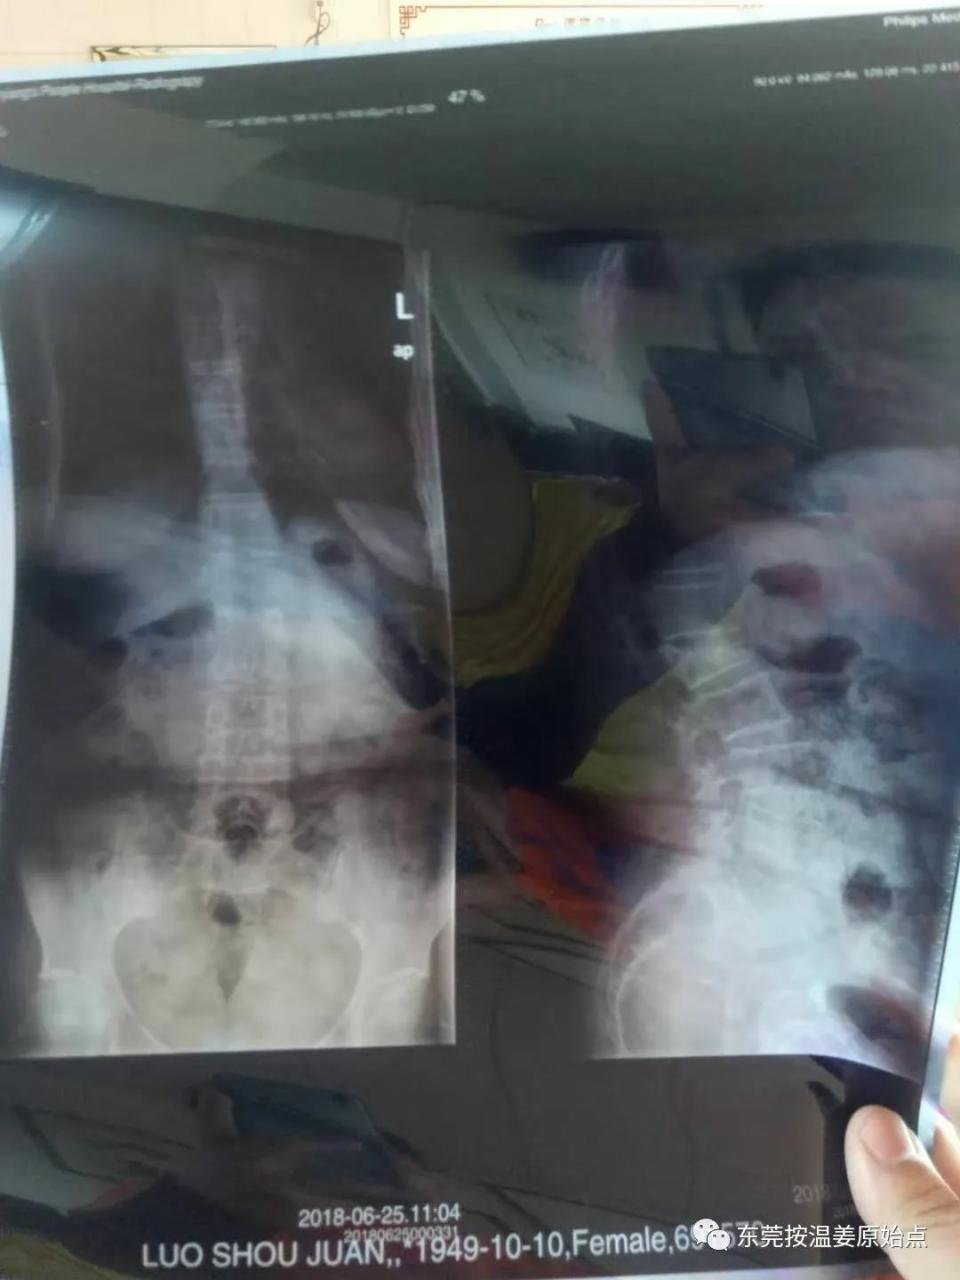

罗婆婆,68岁,东莞石碣人,2018年6月25号因经常腰痛去医院检查,影像表现:胸腰段序列连续,曲度后凸,L1椎体压缩变扁,各椎体边缘变尖,各椎体间隙未见明显变窄。影像诊断:L1椎体压缩性改变,腰椎退行性变,曲度后凸。